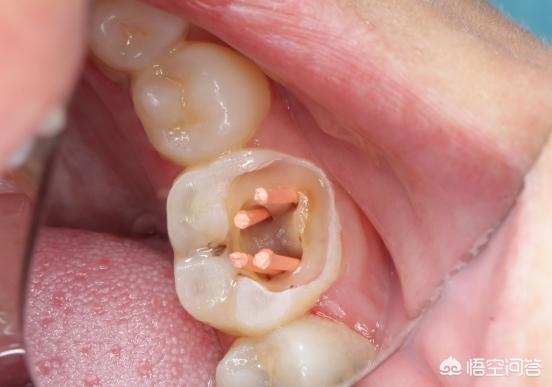

牙神经会跟着患牙离开牙槽骨,因为牙神经在牙体内部的,根部以下的是神经管,像拔下颌智齿的话,如果长在神经管里,手术就有可能损伤到,就会下巴麻木,所以牙神经和神经管是两回事,虽然没拔前是有连在一起的,但拔完牙神经失活,牙体颜色变灰。

2、如果是细菌伤到牙神经,智齿会引发急性牙髓炎,这种不用根管治疗,直接拔除智齿,换成其他牙齿,还能抽掉牙神经保留牙体,不过没有牙髓,得装上烤瓷牙保护。